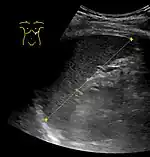

Maximum length of spleen on abdominal ultrasonography